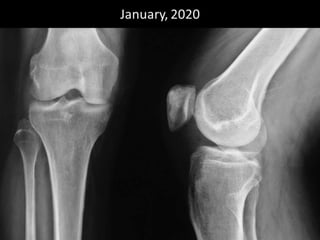

The document presents a detailed case study of a patient with transient osteoporosis of the hip (TOH) and spontaneous osteonecrosis of the knee (SONK) treated at Choithram Hospital & Research Centre in India. Over 20 years, the patient experienced multiple episodes of TOH and SONK with no history of trauma or co-morbidities, resulting in resolutions and recurrences of conditions. The information is intended for orthopedic surgery students and highlights personal experiences and case collections, with a disclaimer regarding content usage and potential controversies.